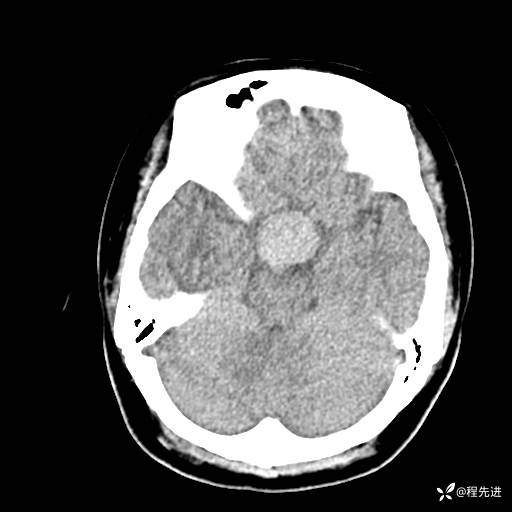

CT平扫: